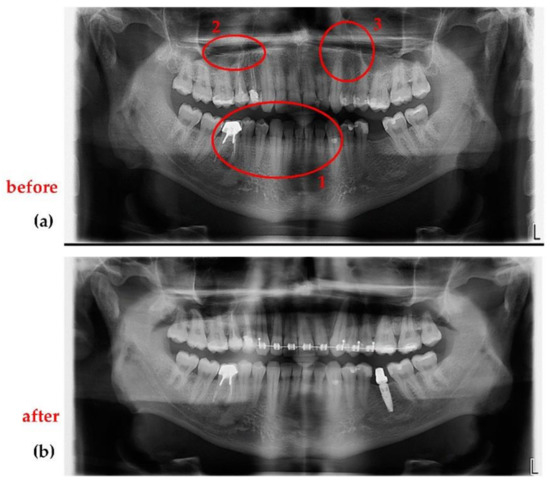

- (4)

- Jewelry or any metal around the head or neck must be taken off, otherwise artifacts may appear on radiographs (Figure 17a). This is a general requirement, irrespective of the calibration procedure using OCT. On the other hand, implants and some materials used for dental crowns or dental fillings do not produce artifacts or sparkles around them on radiographs, as shown in the example in Figure 17b. This latter aspect must be considered during calibrations.